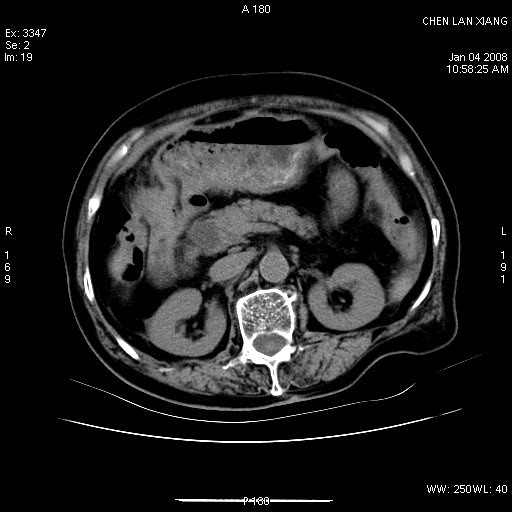

女,76岁,腹痛3-4天,b超示:肝内实性肿物,胆囊强回声,胆总管扩张.

考虑:1、胆总管下端结石伴梗阻性肝内外胆管扩张(肝左叶外侧段肝内胆管多发结石、胆管炎);

胆总管及肝内胆管扩张

胆囊内结增强影,肝内胆管、胆总管扩张明显。肝内胆管、胆总管下段多发结石,胆囊癌,建议mrcp检查

胆总管及肝内胆管多发性结石并扩张。

ct所见:1、 肝内胆管结石,肝内外胆管扩张。低位胆道梗阻,胆总管下端结石;2 胆囊扩大,胆囊壁不规则增厚

考虑:胆总管下端结石并肝内外胆管扩张,肝内胆管结石;